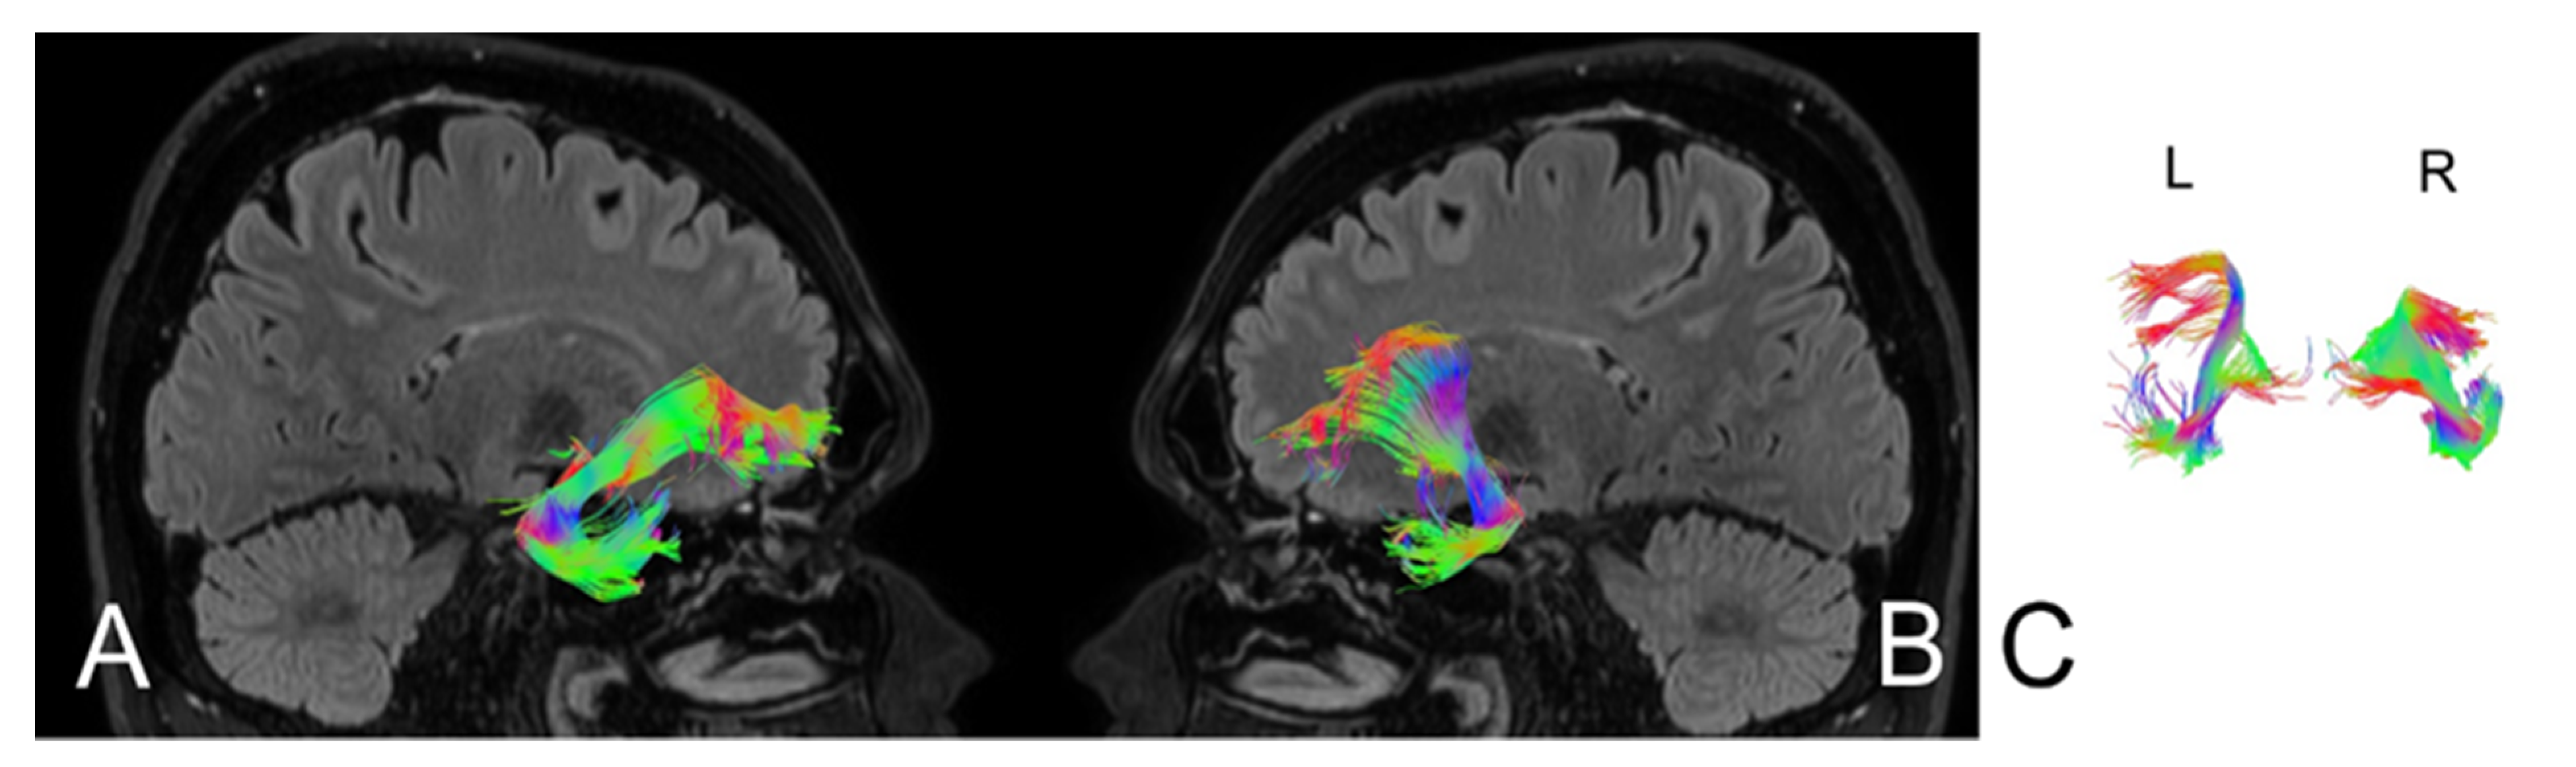

| Number of fibres | 160 | 205 | 185 | 208 |

| Volume of tract [mm2] | 1125 | 18440 | 1280 | 18559 |

| Length of tract [mm] | 75.5 | 88.0 | 86.4 | 89.0 |

| FA | 0.715 | 0.885 | 0.785 | 0.880 |